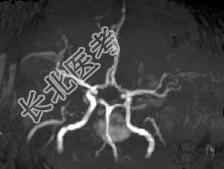

- 单项选择题男,42岁, 头晕视物旋转,面部麻木半月余, 根据所提供图像,最可能的诊断是 ( )

A、脑干动静脉血管畸形

B、脑干出血

C、脑干血管瘤

D、脑干胶质瘤并出血

E、脑干梗死